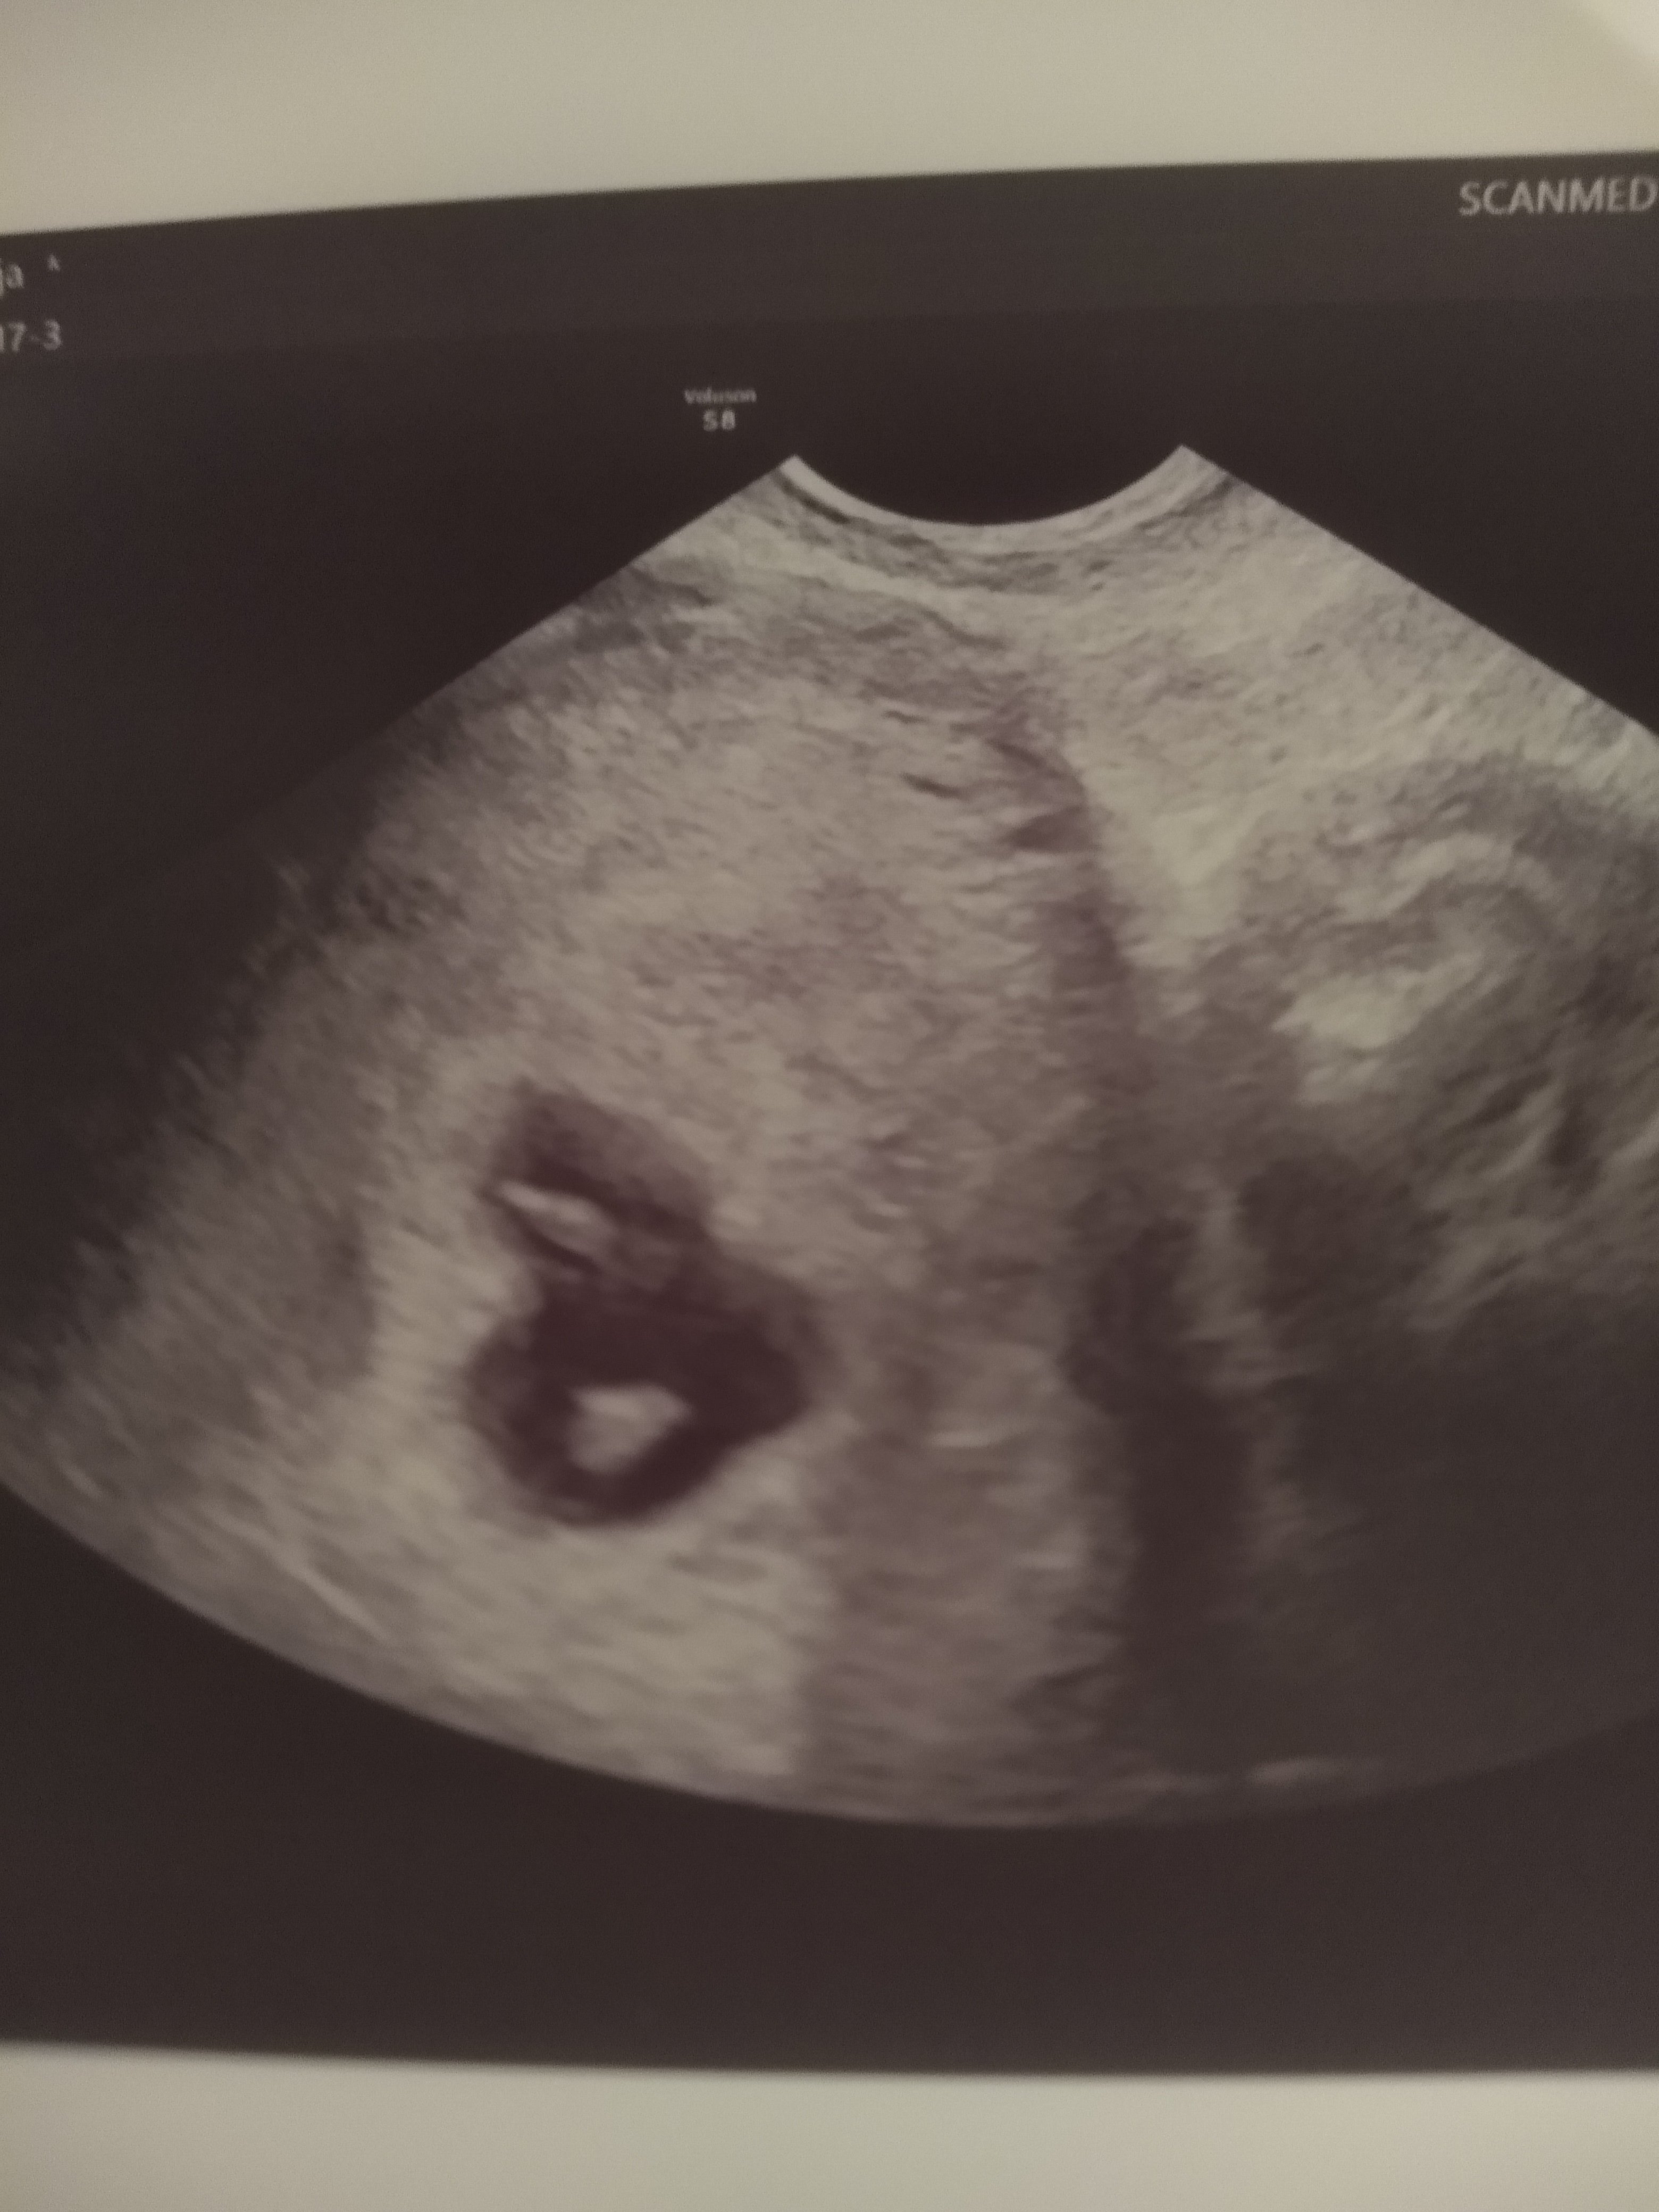

Cześć, to może i ja się przywitam. To moja 6 ciąża, mam dwoje dzieci- synka 7 lat i córcię 5 lat. Bardzo chcieliśmy z mężem trzecie dziecko ale niestety w zeszłym roku straciłam ciążę z synkiem w 17 tygodniu. Od tamtej pory miałam wiele zawirowań hormonalnych i nagle okazało się, że przywieźliśmy z wakacji dodatkowych pasażerów, bo zarodki są dwa! Na razie to jest bardzo wczesna ciąża , 6 tydzień , chociaż było już widać serduszka... Wiem że jeszcze różnie może się potoczyć. Na razie jesteśmy w szoku że to ciąża bliźniacza, wstępny termin wyliczony przeze mnie to 17.05. Mam 38 lat, nadciśnienie, Hashimoto, i jak się okazało dużą torbiel na jajniku